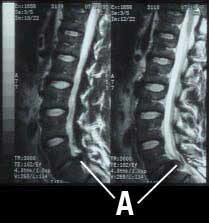

I went to a radiology clinic in Hamburg for the MRI. I spent 10 minutes in a tight tube with flashing lights and loud pounding (rather like a techno show), and within minutes the radiologist showed me a 3 mm extrusion from my L5-S1 vertebrae (very much like the picture here (Fig. 2)). We proceeded immediately to the PRT (my orthopedist is conveniently at the radiologist on Monday afternoons). My fear of the injection was totally unfounded. An initial scan to mark the point, an initial injection, an additional scan to confirm the position, and the injection was finished. I felt almost nothing, and the doctor said his aim was perfect. Within 20 minutes 90% of my pain was gone.